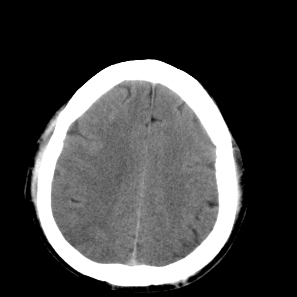

标题: CT18598:男47岁头晕头痛,烦操不安 [打印本页]

标题: CT18598:男47岁头晕头痛,烦操不安

右侧颞顶枕叶缺血性脑梗塞可能性大,建议增强进一步检查。

右侧颞顶叶脑沟变浅,片状低密度区内见略高密度影,考虑出血性脑梗塞,及时复查.

右侧颞顶枕叶脑梗塞可能性大,建议增强进一步检查

右侧颞顶枕叶缺血性脑梗塞可能性大,建议增强进一步检查排除转移瘤。

右大脑多处低密度水肿灶,无明显占位效应,病灶分布于不同大脑动脉供血区域!多发性脑转移瘤.(ct+或mri可进一步验证).

考虑右侧颞顶枕叶交界处脑梗塞可能性大。

考虑分水岭梗塞,建议增强排除其他

右侧颞顶枕叶缺血性脑梗塞